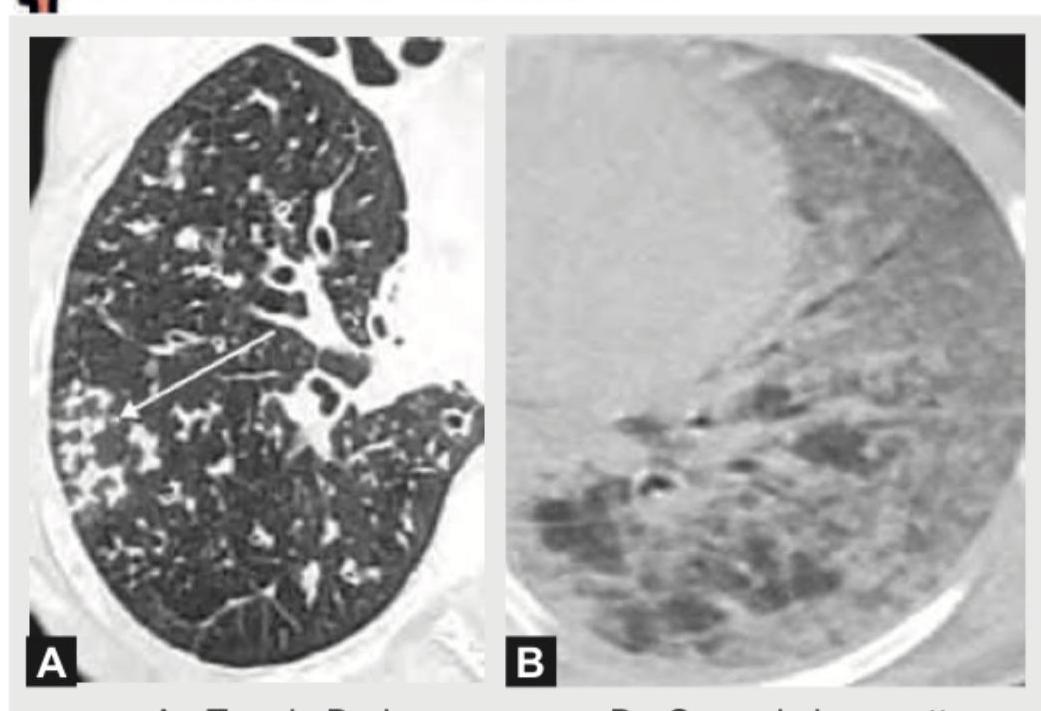

Explanation: ***Option A: A= Tree in Bud appearance, B= Ground glass pattern*** - Image A clearly shows the **"tree-in-bud" appearance**, characterized by small centrilobular nodules and branching linear opacities, which is indicative of filling of the small bronchioles with mucus, pus, or fluid and is commonly seen in infectious or inflammatory conditions. - Image B presents a **ground glass pattern**, which is a hazy increase in lung attenuation with preservation of bronchial and vascular margins, suggesting partial filling of air spaces or interstitial thickening without obscuring the underlying structures. *Option B: A= Crazy pavement pattern, B= Tree in bud appearance* - While "tree-in-bud" is correctly identified for image A, **image B does not show a "tree-in-bud" appearance**. - The "crazy paving pattern" refers to ground-glass opacities superimposed on thickened interlobular septa, which is not depicted in either image. *Option C: A= Mosaic perfusion pattern, B= Crazy pavement pattern* - Image A does not show a **mosaic perfusion pattern**, which is characterized by areas of varying attenuation due to regional differences in lung perfusion and air trapping. - Image B does not represent a **crazy pavement pattern**, as it lacks the clear visualization of thickened interlobular septa within the ground-glass opacities. *Option D: A= Bronchovascular nodular pattern, B= Ground Glass pattern* - While image B correctly identifies the **Ground Glass pattern**, the description for image A as a **bronchovascular nodular pattern** is too broad and imprecise. - The specific morphology in image A, with its branching and nodular opacities, is best described by the "tree-in-bud" appearance rather than a generic bronchovascular nodular pattern.